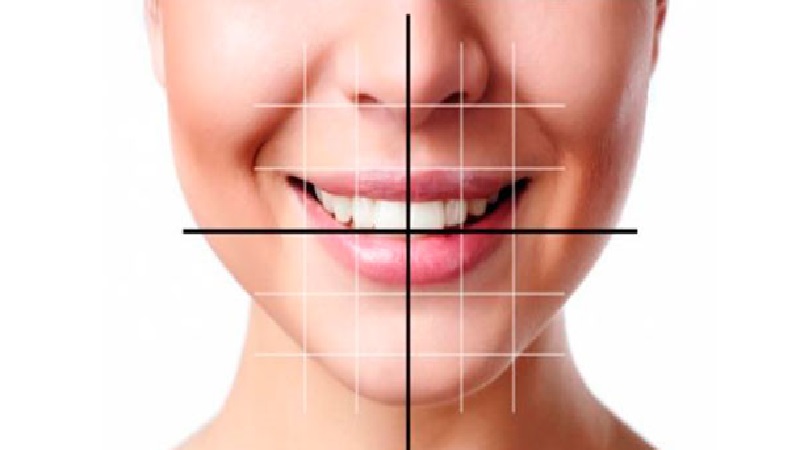

اطلاعاتی پیرامون اصلاح طرح لبخند

آنچه در اصلاح طرح لبخند باید بدانیم !

دندانپزشک متخصص برای ارزیابی و زیبا شناسی طراحی طرح لبخند روش ها و ویژگی های زیادی را باید مورد ارزیابی قرار دهد تا به خوبی اصلاح انجام گیرد که عبارتند از :

تناسب دندان برای اصلاح طرح لبخند

متخصص باید با معاینه کردن تناسب دندان ها را تشخیص دهد و اینکه دندان های جلویی فک بالا که مرکزی هستند و نسبت 4 به 5 را از نظر عرض به طول دارند. متخصص باید مهارت زیباشناسی را داشته باشد تا تعادل مورد نیاز را برای رسیدن به طراحی لبخند را بدهد.